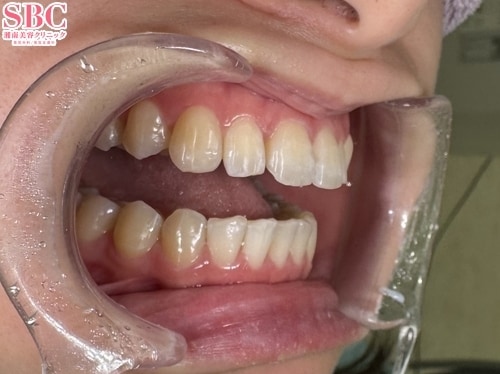

No.340826【美容歯科】【れいな先生】条件次第でここまで引っ込む?!突出感バスターDRれいな☆【マウスピース矯正】

施術前

前歯の突出感が気になる

施術後5ヶ月後

ここまで変わりました

こちらの症例はインビザライン・ゴー両顎の症例になります

前歯2本の突出感がお悩みで、部分矯正のご希望でした。

本来全体矯正で治すべき症例ですが、お客様のご要望に合わせできる範囲で最大限の変化が出るようにさせていただき、

ここまで綺麗な引っ込める矯正が可能になりました。